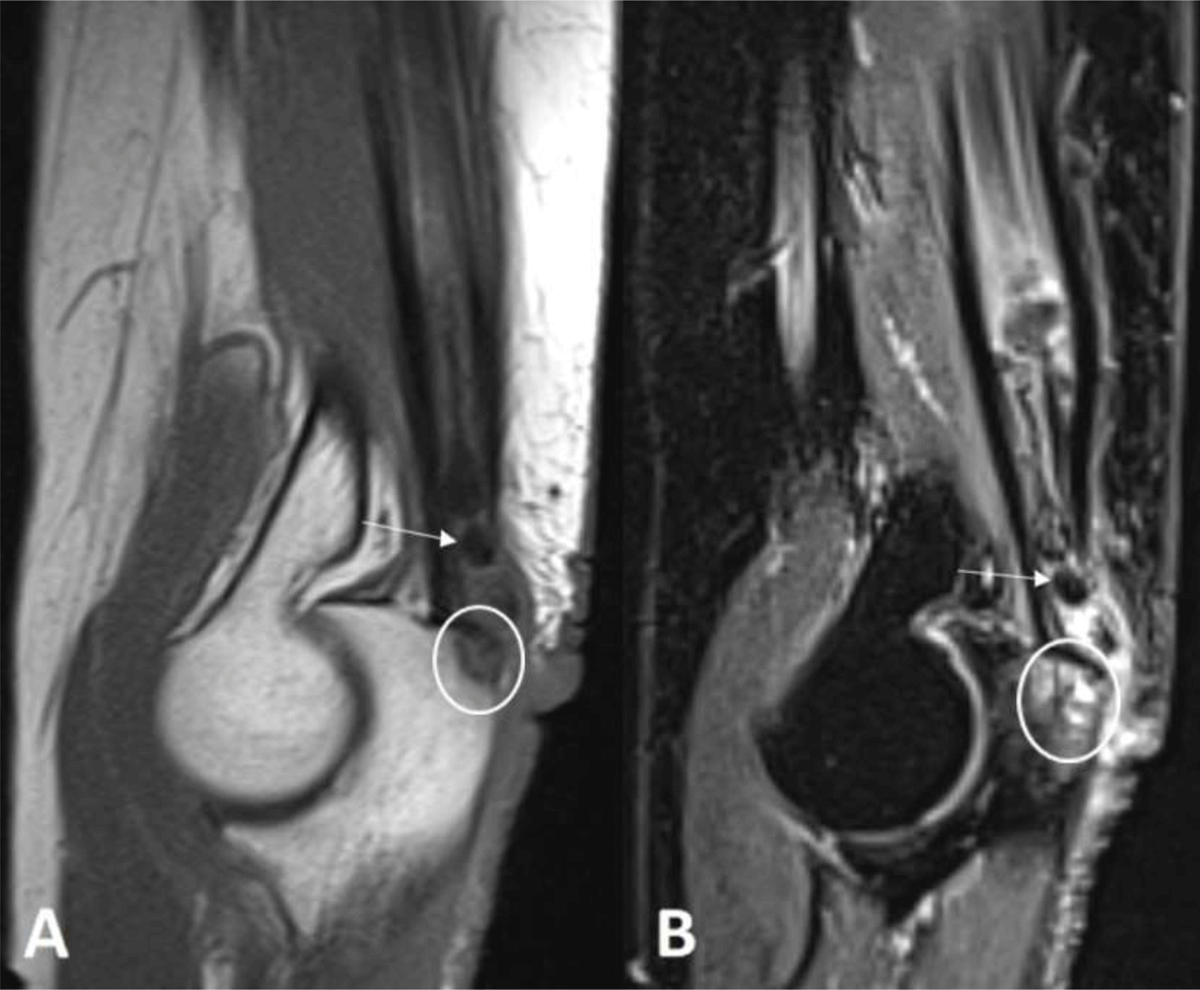

A 68-year-old woman was referred to our department, because of a painful swelling at the extensor side of the right elbow. Magnetic resonance imaging (MRI) revealed an elongated lesion with rosary morphology in the distal triceps muscle belly and tendon. The lesion was predominantly of low signal on all pulse sequences (Figure 1, white arrow) surrounded by hyperintense edema on fat-suppressed (FS) T2-weighted images (WI). There was a focal bony lesion on the triceps tendon insertion (Figure 1, white circle), hyperintense on FS T2-WI and hypo-intense on T1-WI, though surrounded by a subtle peripheral rim with a lower signal. FS T2-WI demonstrated perilesional bone marrow edema.

Figure 1